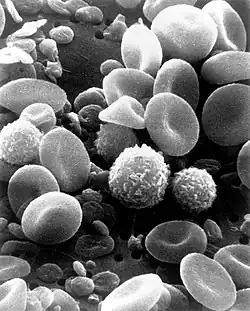

В 1675 году итальянский врач Марчелло Мальпиги (а в 1681 году — и английский ботаник Неемия Грю) подтвердил клеточное строение растений. О клетке стали говорить как о «пузырьке, наполненном питательным соком». В 1674 году голландский натуралист Антони ван Левенгук с помощью микроскопа впервые увидел в капле воды «зверьков» — движущиеся живые организмы (инфузории, амёбы, бактерии). Он также впервые наблюдал животные клетки — эритроциты и сперматозоиды. Таким образом, к началу XVIII века учёные знали, что под большим увеличением растения имеют ячеистое строение, и видели некоторые организмы, которые позже получили название одноклеточных. В 1802—1808 годах французский исследователь Шарль-Франсуа Мирбель установил, что растения состоят из тканей, образованных клетками. Ж. Б. Ламарк в 1809 году распространил идею Мирбеля о клеточном строении и на животные организмы. В 1825 году чешский учёный Ян Пуркине открыл ядро яйцеклетки птиц, а в 1839 ввёл термин «протоплазма». В 1831 году английский ботаник Роберт Броун впервые описал ядро растительной клетки, а в 1833 году установил, что ядро является обязательной органеллой клетки растения. С тех пор главным в организации клеток считается не оболочка, а содержимое.

В 30-х годах XX века был сконструирован электронный микроскоп, в котором вместо света через объект пропускается пучок электронов. Теоретический предел разрешения для современных электронных микроскопов составляет около 0,002 нм, однако из практических причин для биологических объектов достигается разрешение только около 2 нм. С помощью электронного микроскопа можно изучать ультраструктуру клеток. Различают два основных типа электронной микроскопии: сканирующую и трансмиссионную. Сканирующая (растровая) электронная микроскопия (РЭМ) используется для изучения поверхности объекта. Образцы зачастую покрывают тонкой плёнкой золота. РЭМ позволяет получать объёмные изображения. Трансмиссионная (просвечивающая) электронная микроскопия (ПЭМ) — используется для изучения внутреннего строения клетки. Пучок электронов пропускается через объект, предварительно обработанный тяжёлыми металлами, которые накапливаются в определённых структурах, увеличивая их электронную плотность. Электроны рассеиваются на участках клетки с большей электронной плотностью, в результате чего на изображениях эти области выглядят темнее[3][4].